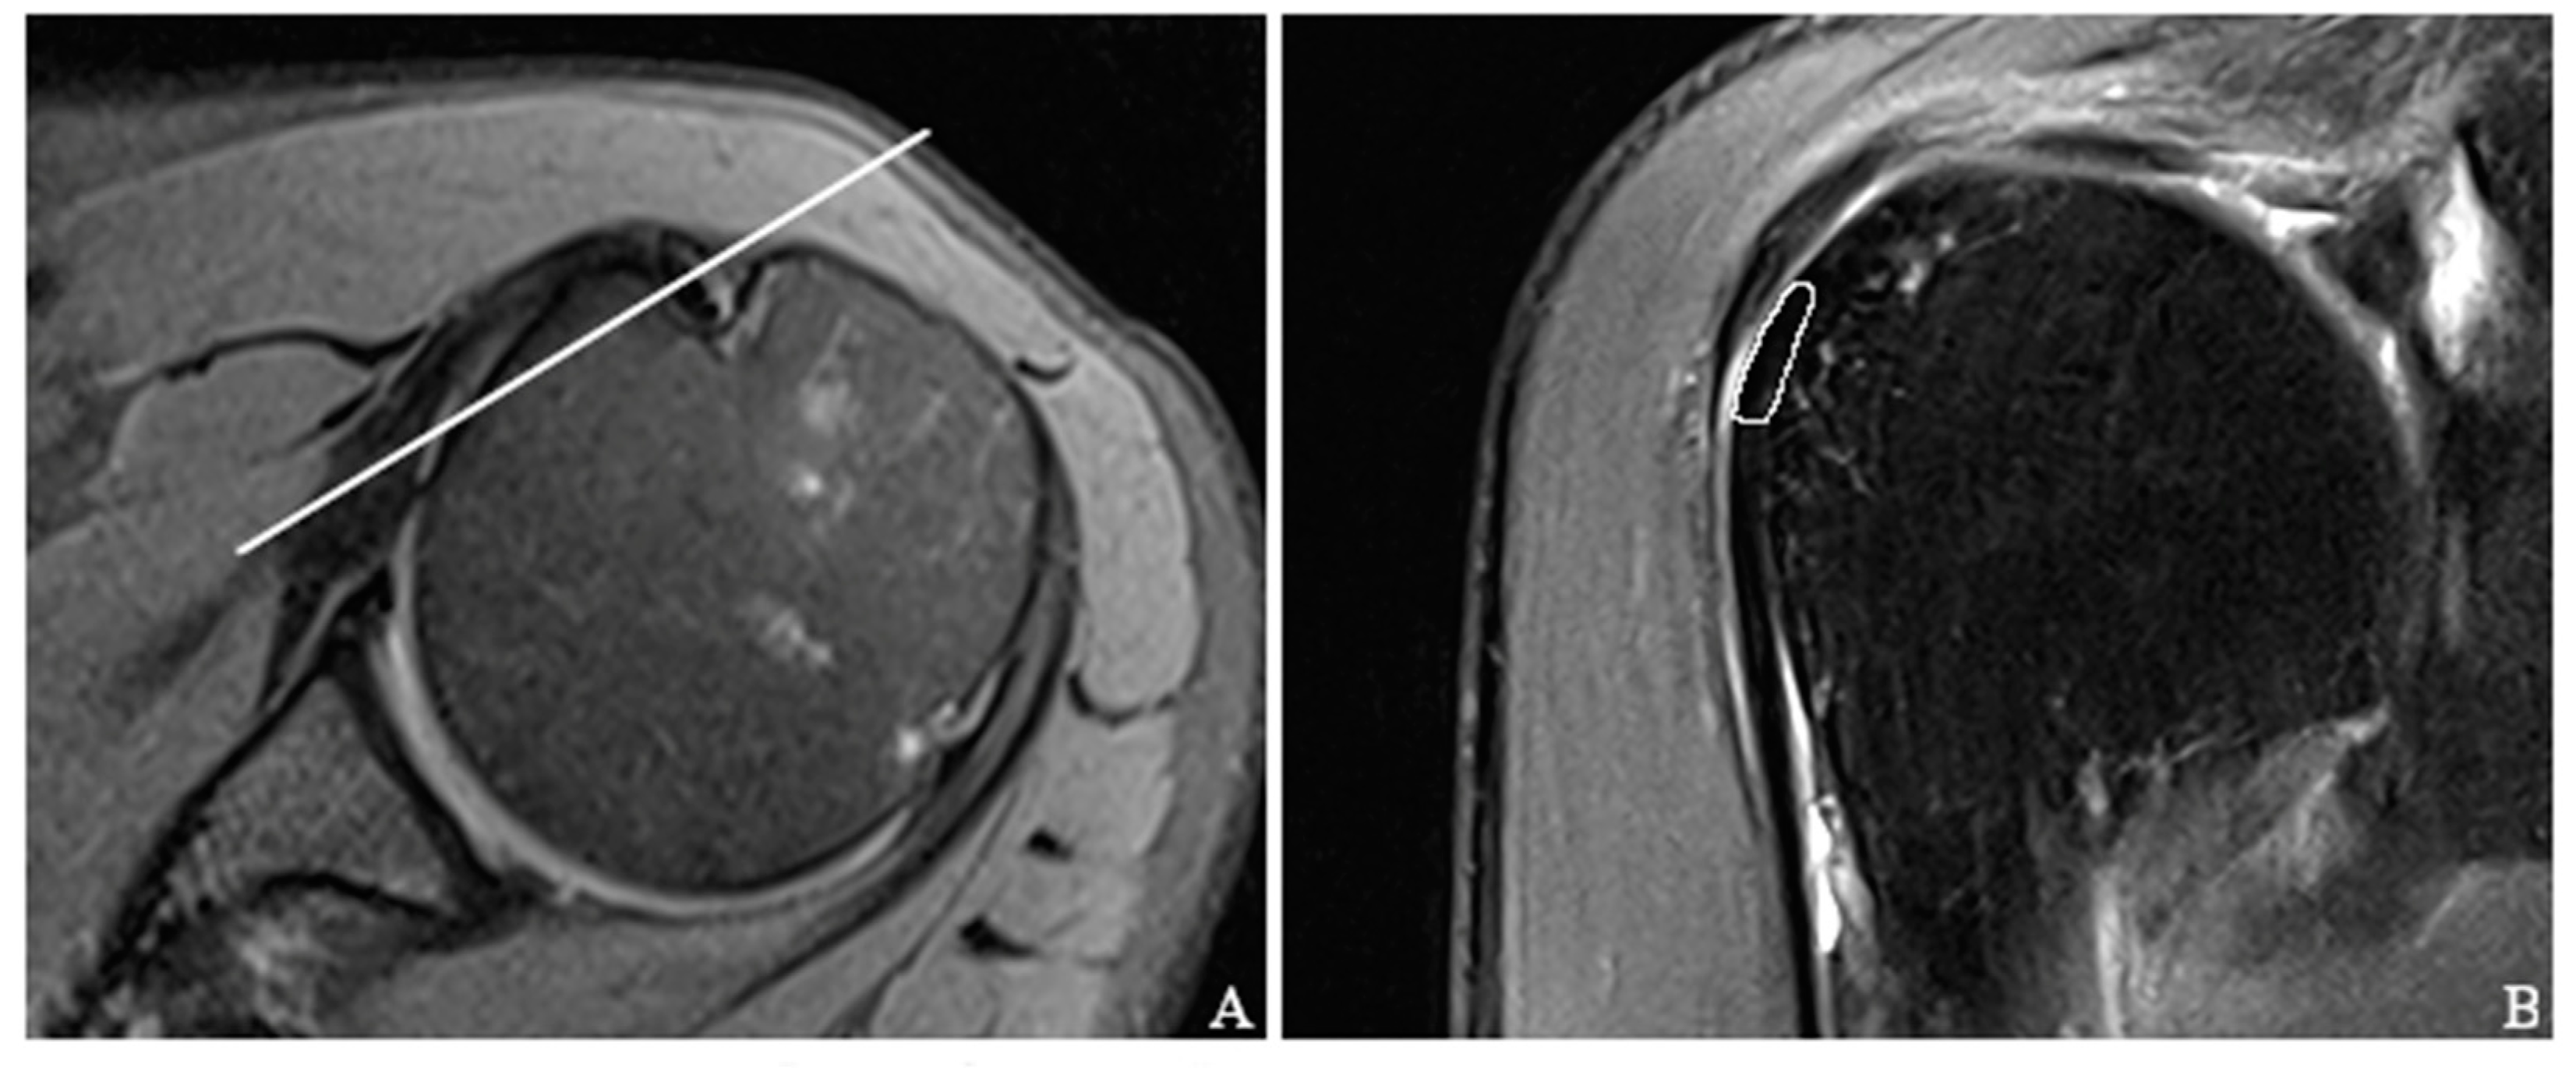

2.3. MRI Protocol and T2 Mapping

2.4. Image Analysis and Definition of LBT Pathologies

2.5. Placement of Regions of Interest